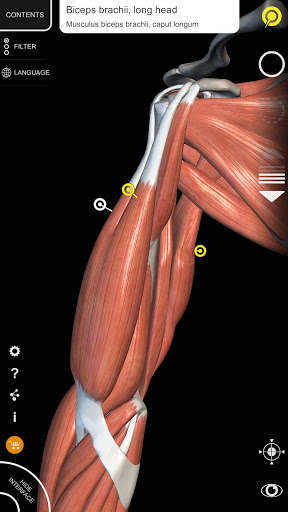

"Anatomía - Atlas 3D" permite estudiar la anatomía humana de forma fácil e interactiva.

A través de una interfaz sencilla e intuitiva es posible observar cada estructura anatómica desde cualquier ángulo.

Los modelos anatómicos 3D son especialmente detallados y con texturas de hasta una resolución de 4k.

nervioso • Sistema respiratorio • Sistema digestivo • Sistema urogenital (masculino y femenino) • Sistema endocrino • Sistema linfático • Sistema ocular y auditivo CARACTERÍSTICAS • Interfaz sencilla e intuitiva • Rotar y hacer zoom en cada modelo en el espacio 3D • Opción para ocultar o aislar uno o varios modelos seleccionados • Filtro para ocultar o mostrar cada sistema • Función de búsqueda para encontrar fácilmente cada parte anatómica • Función de marcador para guardar vistas personalizadas • Rotación inteligente que mueve el centro de rotación automáticamente • Función de transparencia • Visualización de músculos a través de niveles de capas desde las superficiales hasta las más profundas • Al seleccionar un modelo o un pin, aparece el término anatómico relacionado • Descripción de los músculos: origen, inserción, inervación y acción • Mostrar/ocultar interfaz de usuario (muy útil con pantallas pequeñas) MULTILINGÜE • Los términos anatómicos y la interfaz de usuario están disponibles en 11 idiomas: latín, inglés, francés, alemán, italiano, portugués, turco, ruso, español, Chino, japonés y coreano • Los términos anatómicos se pueden mostrar en dos idiomas simultáneamente REQUISITOS DEL SISTEMA • Android 8.0 o posterior, dispositivos con al menos 3 GB de RAM Reversi